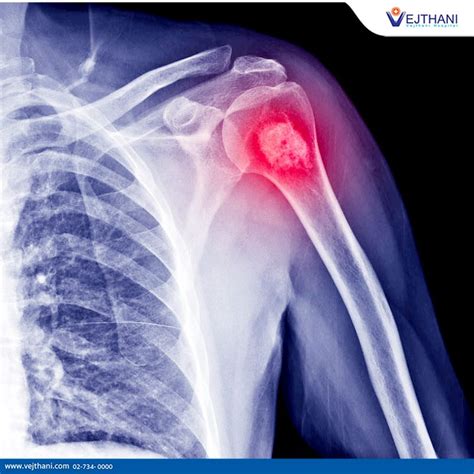

Hey guys, let’s dive into osteosarcoma , a topic that might sound a bit intimidating, but understanding it is super important, especially when we’re talking about cancer. So, what exactly is osteosarcoma? Essentially, it’s a type of bone cancer that typically starts in the long bones of the arms or legs, but it can also occur in other bones, including the pelvis, and even the jaw. What makes osteosarcoma particularly noteworthy is that it’s the most common type of bone cancer found in children and young adults. This is a crucial piece of information because it highlights the need for early detection and effective treatment strategies tailored for this demographic. The American Cancer Society provides a wealth of information on osteosarcoma, and it’s a great resource for anyone looking to get a deeper understanding of this disease. They break down complex medical information into digestible pieces, making it accessible to patients, their families, and even healthcare professionals who want to stay updated. When we talk about osteosarcoma, we’re referring to a cancer that originates from the bone-forming cells, known as osteoblasts. These cells normally help create new bone tissue, but in osteosarcoma, they grow abnormally and uncontrollably, forming a malignant tumor. This abnormal growth can then invade surrounding tissues, and in some cases, it can spread, or metastasize, to other parts of the body, most commonly to the lungs. The aggressive nature of osteosarcoma is one of the primary challenges in its treatment. Early diagnosis is absolutely key, as it significantly improves the chances of successful treatment and a better prognosis. The journey through understanding and battling osteosarcoma can be daunting, but knowledge is power, and the American Cancer Society aims to empower individuals with that knowledge. They cover everything from the signs and symptoms to the diagnostic process, various treatment options, and the ongoing research efforts to find better ways to combat this disease. It’s vital for us to be aware of the potential signs, even if they seem minor at first. Often, the first symptom noticed is pain in the affected bone, which might be mistaken for a sports injury or growing pains in younger individuals. This is why it’s so important not to dismiss persistent pain. The American Cancer Society’s role in disseminating information about osteosarcoma cannot be overstated. They act as a beacon of hope and a reliable source of information in the often confusing landscape of cancer. Their commitment to educating the public and supporting research means that more people are aware of osteosarcoma, leading to earlier diagnoses and ultimately, better outcomes for patients. So, whether you’re a patient, a caregiver, a student, or just someone interested in health, delving into what the American Cancer Society has to say about osteosarcoma is a really worthwhile endeavor. They shed light on the complexities of this bone cancer, offering clarity and guidance to navigate this challenging disease. It’s about fostering a community of informed individuals who can advocate for themselves and their loved ones, and support the ongoing fight against osteosarcoma.

So, you’ve noticed some concerning symptoms, and you’re wondering, “What happens next?” This is where the diagnosis and staging of osteosarcoma come into play, and it’s a critical part of the whole process, as highlighted by the American Cancer Society. Getting a clear diagnosis is the first hurdle, and then understanding the stage helps doctors figure out the best treatment plan. The diagnostic journey usually begins with a thorough physical examination and a detailed discussion about your medical history and symptoms. After that, imaging tests are key. X-rays are often the very first step. They can show abnormal changes in the bone, like a tumor or a fracture. If an X-ray suggests a possible bone tumor, then more advanced imaging techniques are usually ordered. CT scans (Computed Tomography) are excellent for providing detailed cross-sectional images of the bone and surrounding soft tissues. They can help doctors see the size of the tumor and if it has invaded nearby structures. MRI scans (Magnetic Resonance Imaging) are also very important. They give even more detailed images, especially of soft tissues, and are particularly good at showing how far the tumor has spread into the bone marrow or into nearby muscles and blood vessels. Bone scans might also be used. In this test, a small amount of radioactive material is injected into a vein, and it accumulates in areas of increased bone activity, which can highlight the tumor and also show if cancer has spread to other bones. To confirm that it is indeed osteosarcoma and not some other condition, a biopsy is essential. This is where a small sample of the suspected tumor tissue is removed, either through a needle biopsy or a surgical biopsy, and examined under a microscope by a pathologist. The pathologist looks for the characteristic malignant bone cells that define osteosarcoma. This step is absolutely crucial because it confirms the diagnosis and helps determine the specific type and grade of the tumor, which impacts treatment decisions. Once osteosarcoma is confirmed, the next step is staging . Staging is the process of determining the extent of the cancer – how large the primary tumor is, whether it has spread to lymph nodes, and if it has metastasized to distant parts of the body, most commonly the lungs. The American Cancer Society explains that staging helps doctors predict the prognosis and plan the most effective treatment. The most common staging system used for osteosarcoma is the TNM system (Tumor, Node, Metastasis), but for bone cancers, surgeons often use a system that categorizes tumors based on whether they are contained within the bone (localized) or have spread outside the bone (regional or distant). The grade of the tumor is also a critical factor. Tumor grade refers to how abnormal the cancer cells look under a microscope and how quickly they are likely to grow and spread. High-grade tumors are more aggressive and have a poorer prognosis than low-grade tumors. The stage and grade together give doctors a comprehensive picture of the cancer’s status. For example, stage I cancers are typically low-grade and localized, while stage IV cancers have likely metastasized. The American Cancer Society provides detailed information on these stages, helping patients and their families understand what each means for their treatment journey. This detailed diagnostic and staging process is fundamental for tailoring a personalized treatment approach, which is vital for maximizing the chances of successful outcomes in the fight against osteosarcoma.